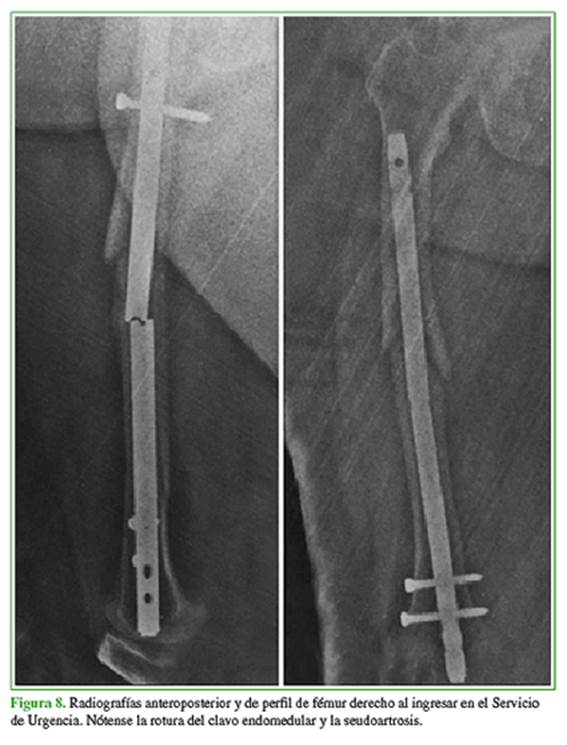

En los controles radiográficos, se observó un retraso de la consolidación y su posterior evolución a la seudoartrosis y la inherente fatiga del clavo endomedular que presentaba un orificio de bloqueo cercano al foco de la fractura. Pero, al no haber síntomas ni dolor, la paciente no aceptó una segunda intervención. Al año de la intervención, ingresó en el Servicio de Urgencia con dolor e impotencia funcional, luego de una caída desde su propia altura. Se observó la rotura del implante (Figura 8).